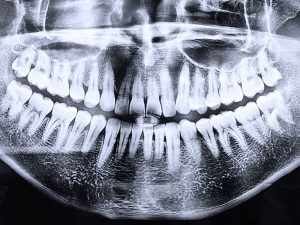

La Importancia de las radiografías en la planificación de cirugías dentales

Las radiografías en la planificación de cirugías dentales son esenciales, más aún cuando se trata de...